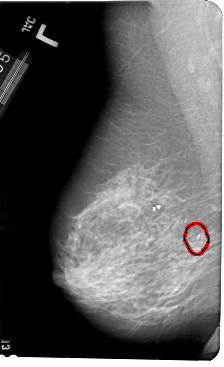

A_1496_1.RIGHT_MLO

RIGHT_MLO LINES 5491 PIXELS_PER_LINE 3361 BITS_PER_PIXEL 12 RESOLUTION 43.5 NON_OVERLAY

FILE: A_1496_1.LEFT_MLO.OVERLAY

TOTAL_ABNORMALITIES 1

ABNORMALITY 1

LESION_TYPE CALCIFICATION TYPE AMORPHOUS DISTRIBUTION CLUSTERED

ASSESSMENT 2

SUBTLETY 5

PATHOLOGY BENIGN

TOTAL_OUTLINES 1